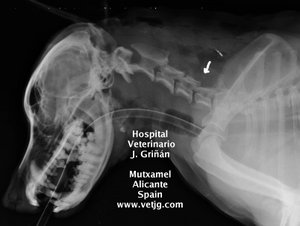

radiografia: imagen del postoperatorio, indicando la zona abordada |

radiografía: imagen del postoperatorio, indicando la zona abordada |